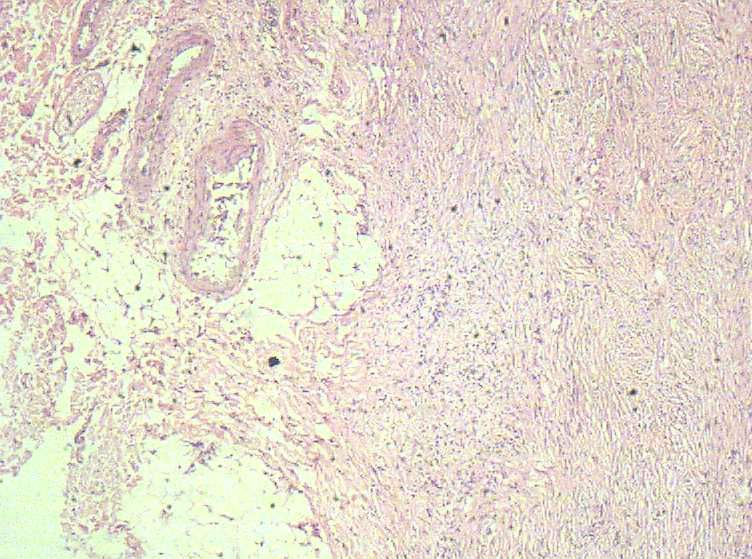

女40岁,发现乳房皮肤表面一年多。

肉眼:不整形组织1.5*1*0.5一侧见皮肤或一侧可见脂肪,切开内一小结节触之稍韧。

• 乳房皮肤表面小结节  请会诊!图3

图3

倾向于皮肤纤维瘤。

皮肤纤维瘤

良性病变。

炎症后的瘢痕结节或者纤维组织瘤样增生?